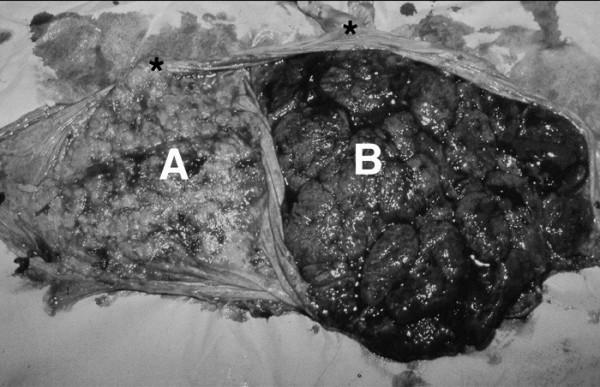

This report describes a patient counseling approach and non-surgical management of a dichorionic-diamniotic twin pregnancy where delivery of the second twin followed the delivery of the first by 110 days. CASE PRESENTATION: An early transvaginal sonogram at 19 1/2 weeks suggested cervical dilation with protruding amniotic membranes. Tocolytic and antibiotic therapy was initiated; no cerclage was placed. Spontaneous rupture of membranes and cord prolapse occurred 48 h later, resulting in delivery of a stillborn female infant. Conservative management was offered after counseling for possible risks associated with maternal sepsis, need for extended hospitalization, potential for hysterectomy and death. The cervix appeared closed after delivery and the umbilical cord was ligated, with subsequent spontaneous cord retraction in utero. Reassuring fetal status was observed for twin B without evidence of contractions or chorioamnionitis. A viable male infant (2894 g) was delivered vaginally at 35 1/2 weeks. CONCLUSIONS: This report outlines a counseling approach useful for patients with premature delivery of one twin, and presents application of conservative obstetrical management principles for the aftercoming twin even when delivery interval is extreme.

本报告描述了对双绒毛膜双羊膜囊双胎妊娠的患者咨询方法及非手术管理,其中第二个胎儿在第一个胎儿分娩后110天出生。病例介绍:孕19 1/2周时的早期经阴道超声检查提示宫颈扩张伴羊膜囊突出。开始使用宫缩抑制剂和抗生素治疗;未行宫颈环扎术。48小时后发生胎膜自然破裂和脐带脱垂,导致一名死产女婴出生。在对与产妇败血症、延长住院需求、子宫切除可能性和死亡相关的可能风险进行咨询后,提供了保守治疗方案。分娩后宫颈似乎闭合,脐带结扎,随后脐带在子宫内自然回缩。观察到双胎B胎儿状况良好,无宫缩或绒毛膜羊膜炎迹象。一名存活男婴(2894克)于孕35 1/2周经阴道分娩。结论:本报告概述了一种对单胎早产患者有用的咨询方法,并介绍了即使分娩间隔极长时,保守产科管理原则对后出生胎儿的应用。